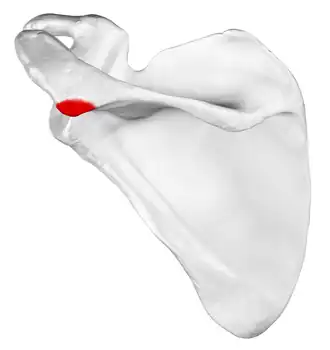

Left scapula, posterior view. Acromion shown in red. | |

Left scapula. Acromion shown in red.

Left scapula. Acromion shown in red. -